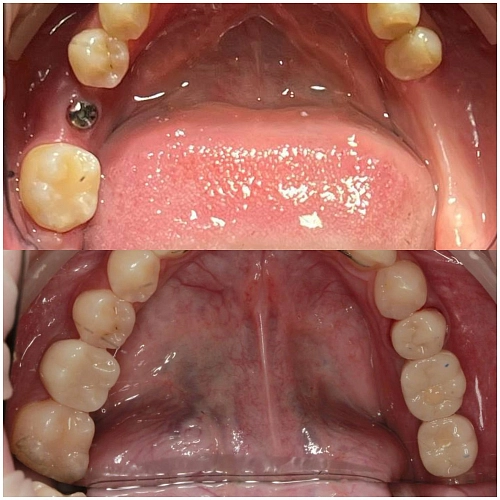

Это время необходимо для того, чтобы имплантат прижился и костная ткань надежно вросла в имплантат. Также важно, чтобы десна зажила, а лунка под коронку сформировалась с помощью формирователя десны .

Когда имплантат успешно прижился и лунка готова, можно переходить к установке коронки!

Ортопед сделает слепок, подберет идеальный цвет будущей коронки и отправит его на изготовление .

После этого пройдет примерка и фиксация!

На фото работа врача-ортопеда Андреева ДП